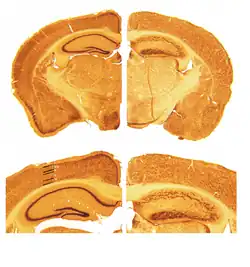

A reeler is a mouse mutant, so named because of its characteristic "reeling" gait. This is caused by the profound underdevelopment of the mouse's cerebellum, a segment of the brain responsible for locomotion. The mutation is autosomal and recessive, and prevents the typical cerebellar folia from forming.

Cortical neurons are generated normally but are abnormally placed, resulting in disorganization of cortical laminar layers in the central nervous system. The reason is the lack of reelin, an extracellular matrix glycoprotein, which, during the corticogenesis, is secreted mainly by the Cajal–Retzius cells. In the reeler neocortex, cortical plate neurons are aligned in a practically inverted fashion ("outside-in"). In the ventricular zone of the cortex fewer neurons have been found to have radial glial processes.[1] In the dentate gyrus of hippocampus, no characteristic radial glial scaffold is formed and no compact granule cell layer is established.[2] Therefore, the reeler mouse presents a good model in which to investigate the mechanisms of establishment of the precise neuronal network during development.

Key pathological findings in the reeler brain structure

- Inversion of cortical layers.

- Dispersion of neurons within cortical layers.

- Decreased cerebellar size.

- Failure of preplate to split

First mention of reeler mouse mutation dates back to 1951.[17] In the later years, histopathological studies revealed that the reeler cerebellum is dramatically decreased in size and the normal laminar organization found in several brain regions is disrupted (Hamburgh, 1960). In 1995, the RELN gene and reelin protein were discovered at chromosome 7q22 by Tom Curran and colleagues.[18]